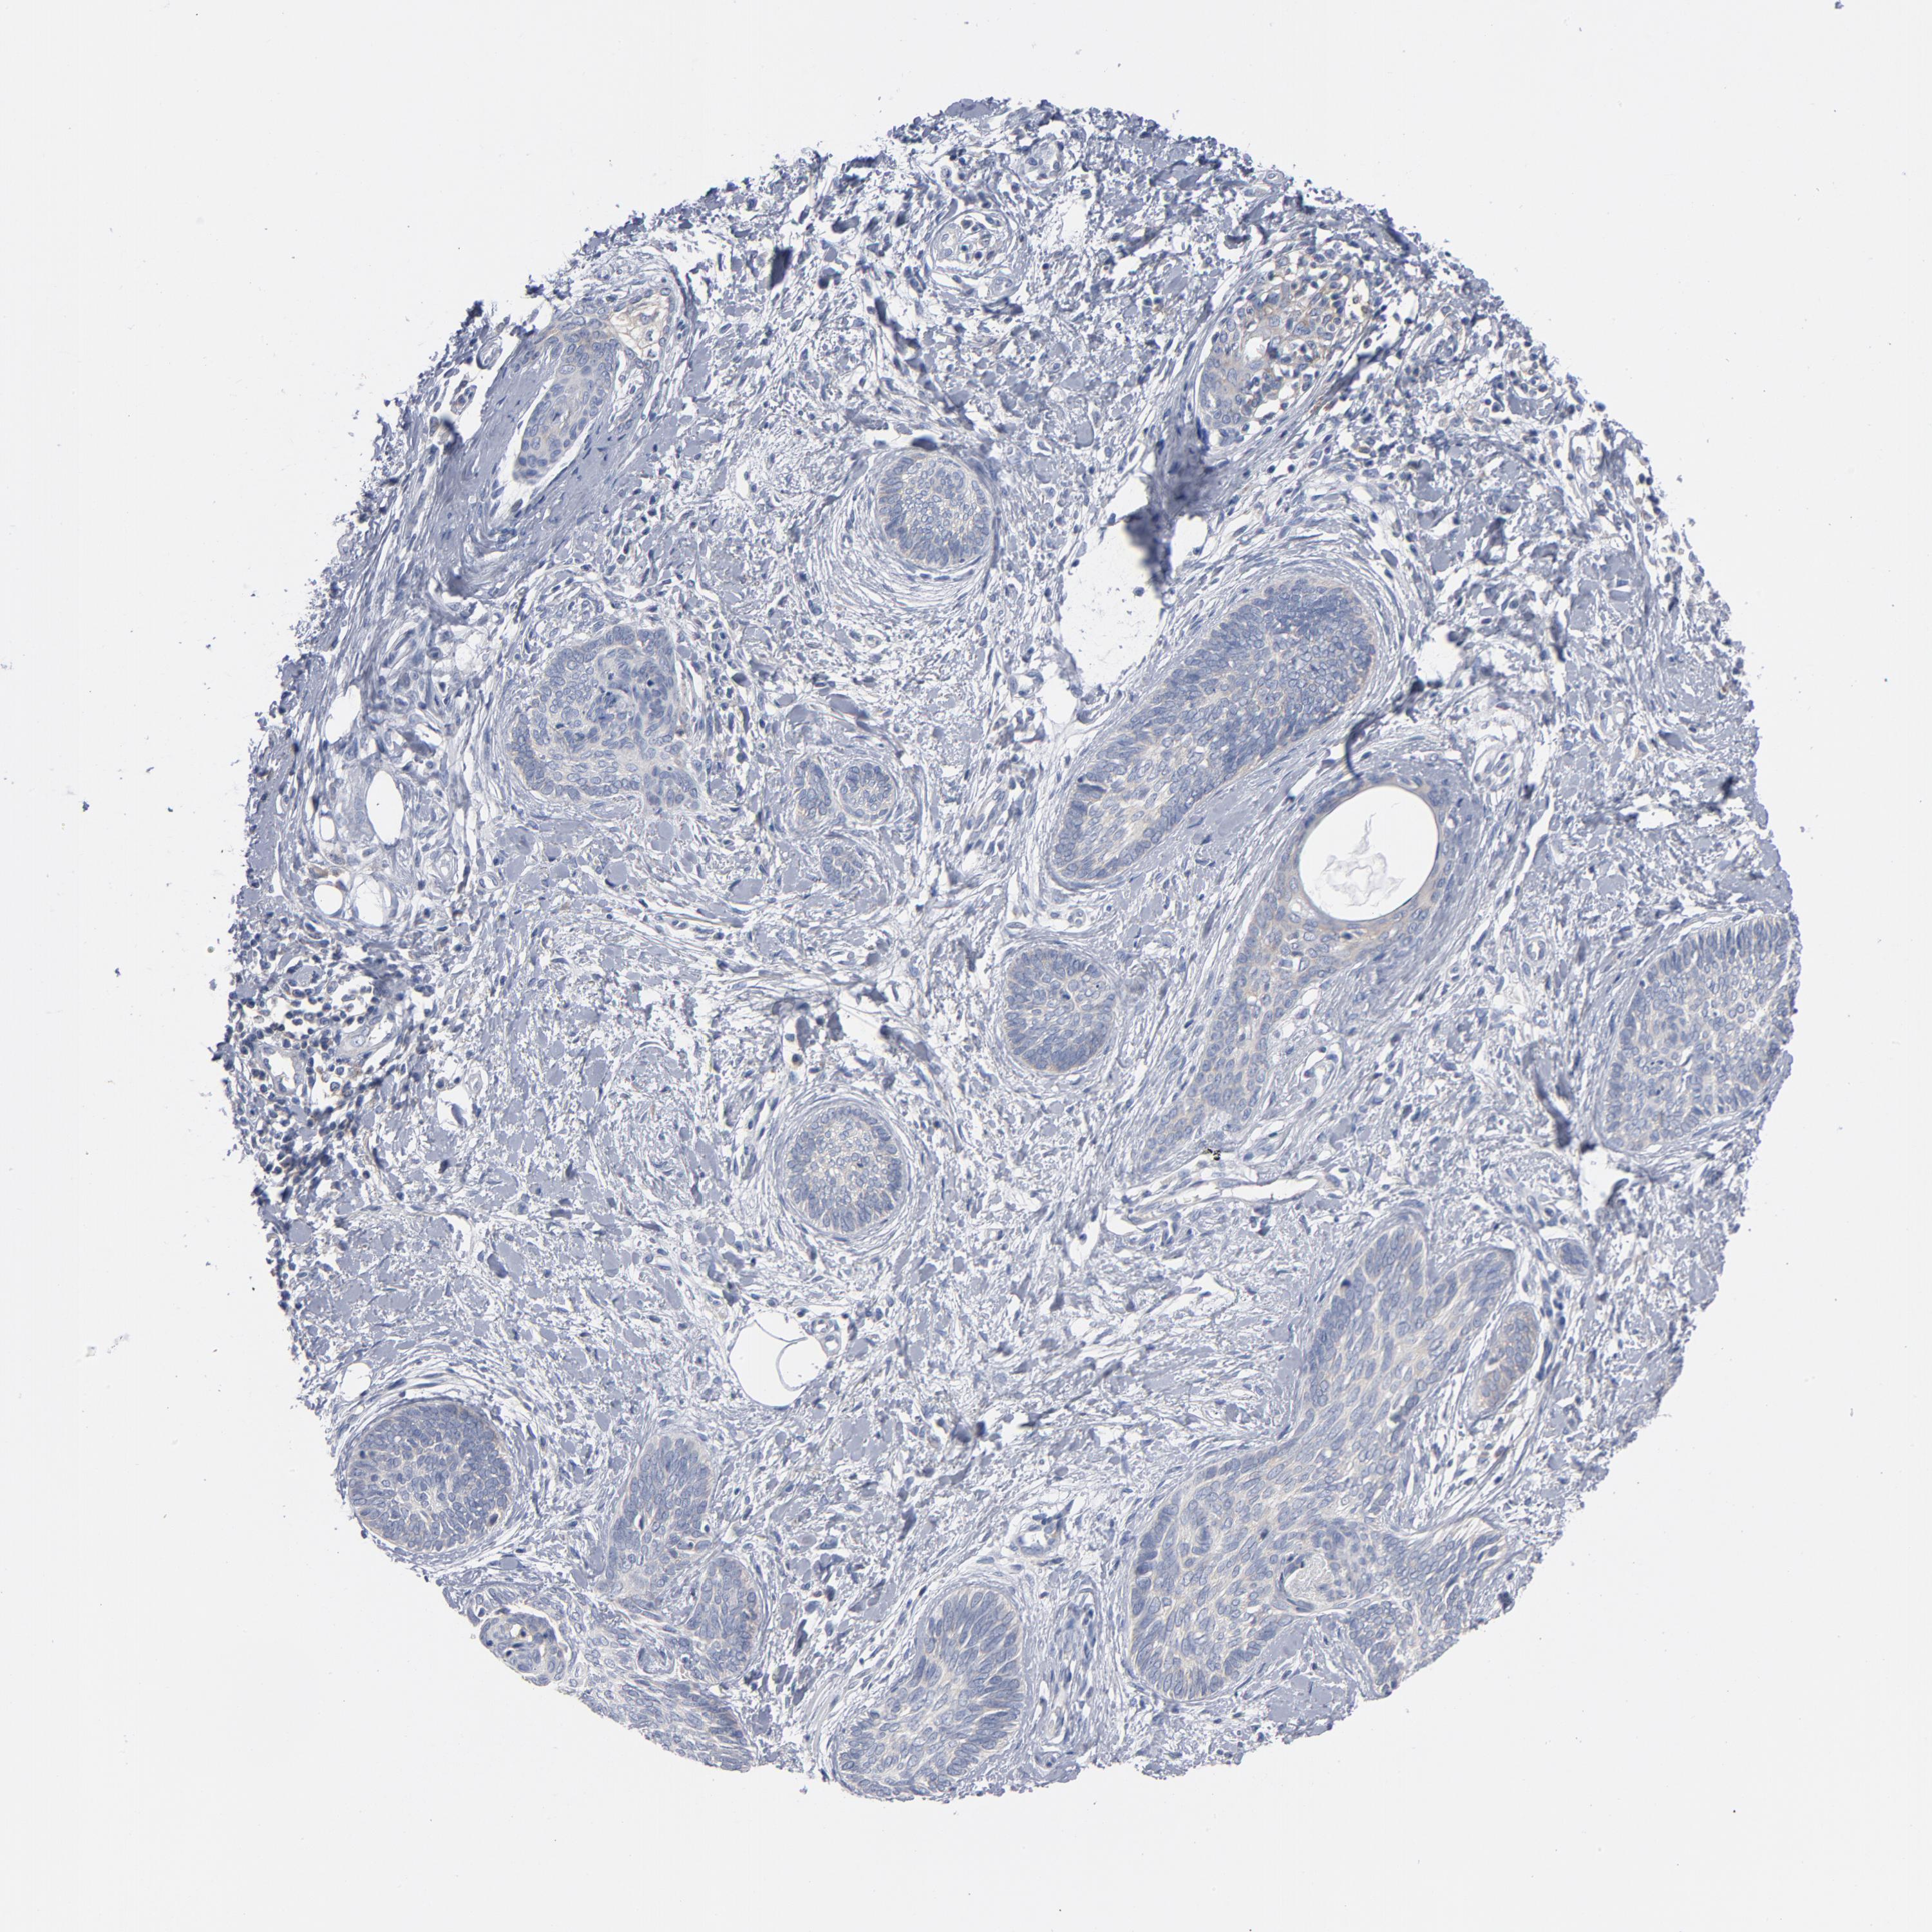

Basal cell and squamous cell cancer

SKIN CANCER - Protein expressioni

A mouse-over function shows sample information and annotation data. Click on an image to view it in a full screen mode. Samples can be filtered based on level of antibody staining by selecting one or several of the following categories: high, medium, low and not detected. The assay and annotation is described here.

Antibody stainingi

Antibody staining in the annotated cell types in the current human tissue is reported as not detected, low, medium, or high, based on conventional immunohistochemistry profiling in selected tissues. This score is based on the combination of the staining intensity and fraction of stained cells.

Each image is clickable and will lead to virtual microscopy that enables deeper exploration of all samples and also displays staining intensity scores, fraction scores and subcellular localization as well as patient and tissue information for each sample.

Antibody CAB004319

Staining

High

Medium

Low

Not detected

Intensity

Strong

Moderate

Weak

Negative

Quantity

>75%

75%-25%

<25%

None

Location

Nuclear

Cytoplasmic/membranous

Cytoplasmic/membranous,nuclear

Squamous cell carcinoma, NOS

Basal cell carcinoma